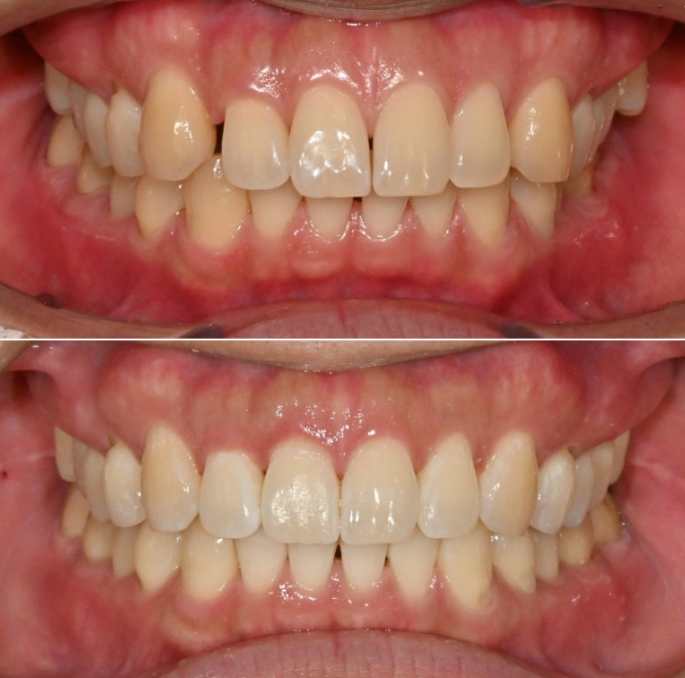

정확히 일치하는 중심선이 눈에 띕니다.

과개교합은 개선되어 이제 아래 앞니가 절반 이상 보입니다.

어금니 교합은 물샐틈 없는 1급 교합관계를 보입니다.

총 치료기간은 11개월에 재제작 1회 입니다.

앞니 사이 벌어진 공간은 없어졌고 다시 벌어지지 않도록 고정식 철사 유지장치로 단단히 고정되었습니다

코와 인중과 어긋나 있던 중심선이 얼굴과 맞아지면서 대칭성이 돋보입니다.

벌어져 있던 앞니공간을 이용하여 돌출감도 어느정도 개선이 되었고

치근흡수 없이 치근평행도도 양호합니다.